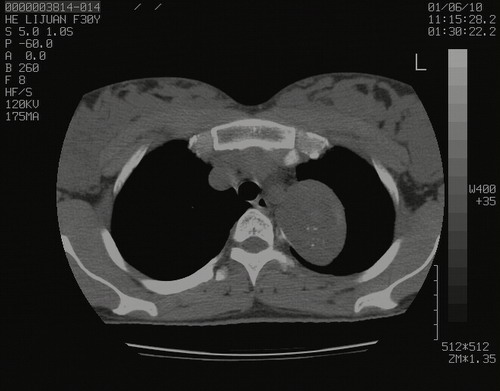

怀孕3个月时(2009-3至4月间),自述突感左侧前后胸疼痛1天,以前胸明显,随后偶感闷痛,余未见异

左肺尖脊柱旁沟肿块,境界清楚,边缘光滑,密度不均,内有多发点片状钙化,考虑良性肿瘤,骨软骨瘤或神经源性肿瘤可能,肺错构瘤不除外。

左后上纵隔见一类圆形肿块影,外侧边界清,密度不均匀,内可见点状钙化影,增强呈不均匀强化,考虑神经源性肿瘤可能。期待病理结果。